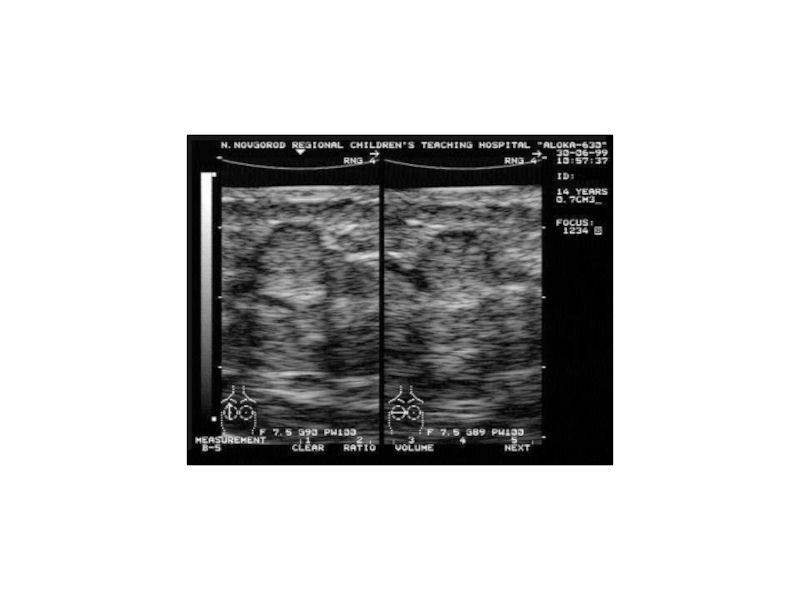

УЗД печінки, нирок, матки і додатків, сечового міхура

УЗД